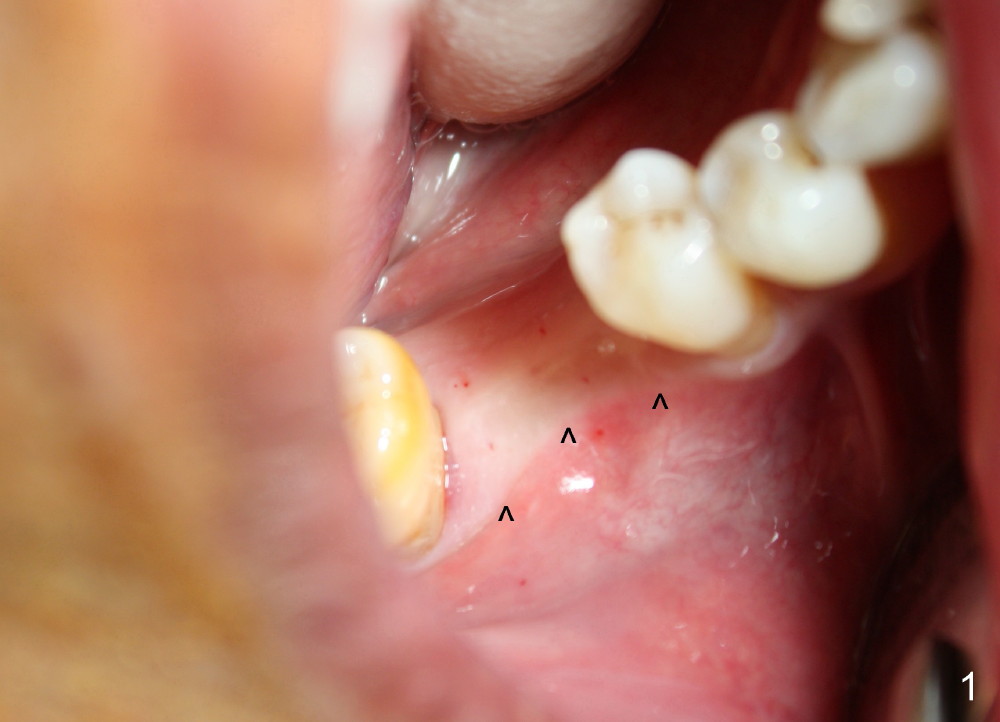

It is critical to identify the inferior alveolar canal (IAC) prior to and during implantation. A 59-year-old man requests implant for the lower right 1st molar (Fig.1). PA taken with a regular sensor holder does not show IAC except part of the mental loop (Fig.2 red dashed line), whereas the one taken with an endo sensor holder does show IAC (Fig.3 yellow dashed line).